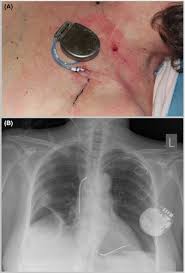

Prevention And Treatment Strategies For Pocket Hematomas During Cied Implantation Pocket Management Systems And Other Adjuvant Interventions Ep Lab Digest

Prevention And Treatment Strategies For Pocket Hematomas During Cied Implantation Pocket Management Systems And Other Adjuvant Interventions Ep Lab Digest from www.eplabdigest.com